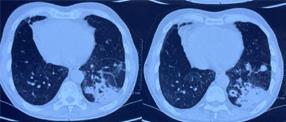

additionally in eight patients to confirm the intraprostatic or extra-prostatic location of the cysts. Ultrasound revealed mixed echogenic masses in all the three patients with retro-vesical teratoma (Fig 3) which was difficult to differentiate from haematoma and four patients had cystic lesion contained hyperechoic material consistent with dermoid cyst but one letter on confirm on HPE was mullerian duct cyst with cystadenoma. A cystic extra-prostatic mass lateral to

Fig 4 — USG images of seminal vesicle cyst Fig 1 — USG images showed prostatic cyst Fig 3 — Radiological images of Teratoma (case no 5)

Fig 2 — Radiological pictures of Epidermoid cyst (case no 3) and Last MRI picture showed b/l seminal vesicle cyst (case no 4)

CT scan and/or MRI abdomen pelvis : CT Scan and/ or MRI abdomen pelvis was performed in 16 cases, both were accurately demonstrated the anatomical relationship of associated intra pelvic organs with surrounding fat and pelvic lymph nodes. CT Scan and/ or MRI abdomen pelvis clearly depicted prostatic utricle cysts in 3/3(100%) cases, intraprostatic abscess cavities in 2/2 (100%) cases, seminal vesicle cysts 2/ 2 (100%) and cystic connective tissue masses in 4/4 (100%). CT scan abdomen pelvis accurately demonstrated retro-vesical connective tissue solid masses in three cases. CT scan and/or MRI abdomen pelvis failed to differentiate accurate diagnosis in two cases (ejaculatory duct cyst and mullerian duct cyst with cystadenoma). However, MRI failed to differentiate between teratoma and haematoma. FNAC accurately demonstrates diagnosis in two cases of intraprostatic abscess (Fig 6).